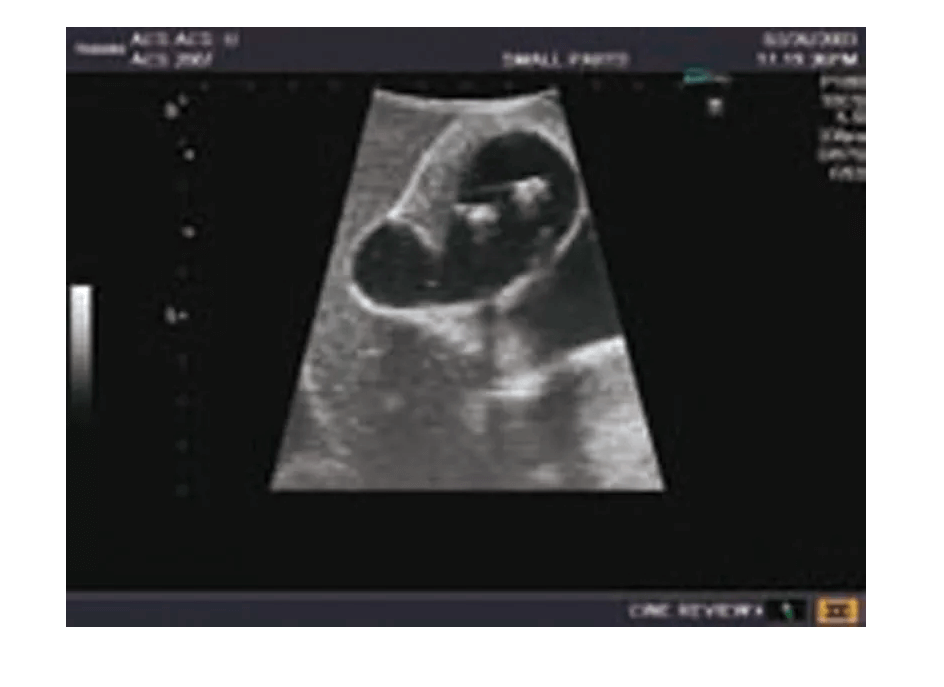

Das Ultraschall-Modell für Sonografie ist speziell für die Ausbildung von Anfängern und die Demonstration durch Fachleute konzipiert. Es bietet eine detaillierte und realistische Darstellung der Anatomie des Abdomens, einschließlich der Leber, Gallenwege, des Pankreas und der Nieren. Das Modell erfüllt die höchsten Anforderungen an eine exzellente Ausbildung und ermöglicht die Durchführung von offenen intraoperativen Sonografien sowie laparoskopischen Untersuchungen, um etwaige Läsionen und Steinbildungen zu prüfen. Es umfasst eine Vielzahl von Läsionen wie Gallensteine, Zysten und Tumore, die in den verschiedenen Organen simuliert sind, um realistische Übungsmöglichkeiten zu bieten.

Demonstration und Übung intraoperativer und laparoskopischer Ultraschalltechniken

Simulieren von Diagnoseverfahren zur Untersuchung von Leber-, Gallen- und Pankreasläsionen

Durchführung von Ultraschalluntersuchungen bei der Diagnostik von Tumoren und anderen pathologischen Befunden

Training für die laparoskopische Ultraschalluntersuchung von Organen und deren strukturellen Anomalien

Simulierte Läsionen (solide Tumore, Zysten, Gallensteine) in wichtigen Organen für praxisnahe Ausbildung

Integrierte Simulation von organischen Läsionen und Tumoren, die in die Organe eindringen, für die Übung und Diagnostik

Die Simulation von pathologischen Befunden wie Tumoren, Zysten und Steinbildungen ermöglicht eine umfassende Vorbereitung auf die Ultraschalldiagnostik